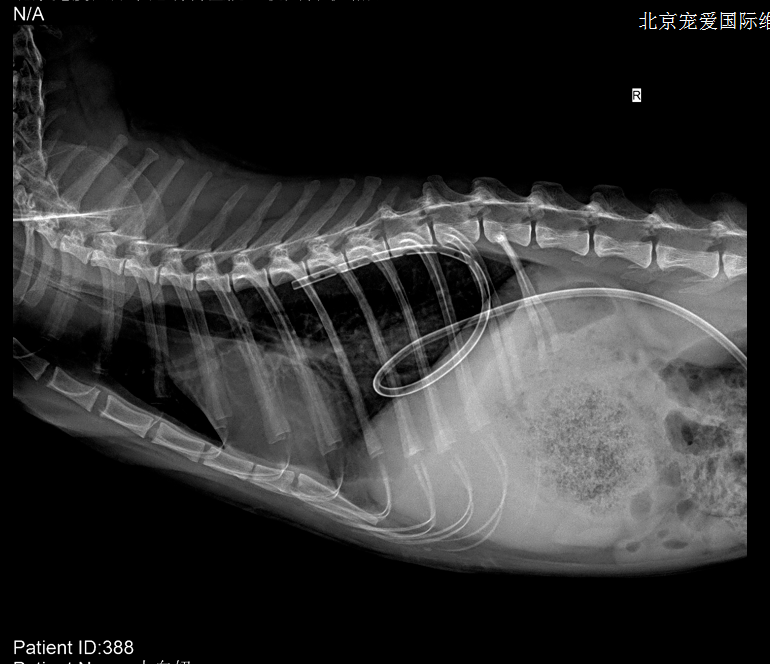

【求助】猫严重胸腔积液,腹部不明团块!

猫胸部侧视图x光片